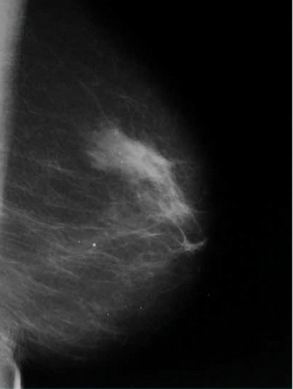

Kazuistika č.2

V HZQ je skupina nově vzniklých tečkovitých mikrokalcifikací,

stejné intra a interkorpukulární denzity, vzhledem k ložiskové

asymetrii ml. žl. hodnoceny jako semimaligní – dle

histologie po exstirpaci po označení vodičem pouze prosté fibrocystické

změny